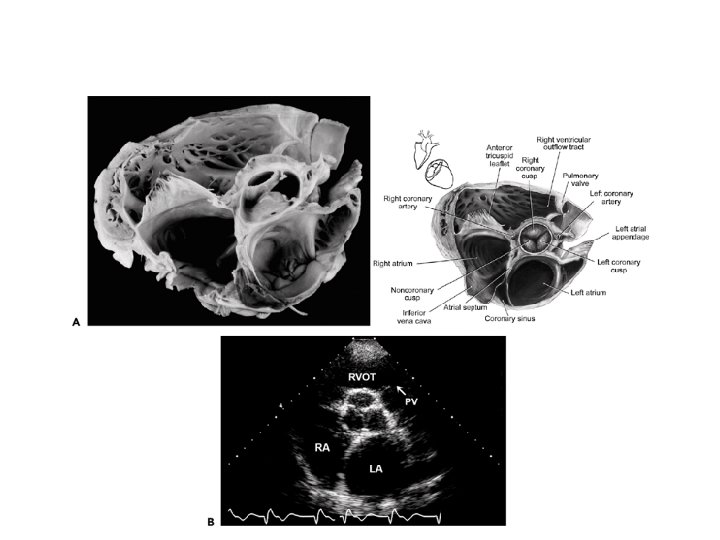

PARASTERNAL SHORT AXIS

PARASTERNAL SHORT AXIS - AT PULMONARY ARTERY BIFURCATION LEVEL

PSAX – LMCA AND RCA VISIBLE